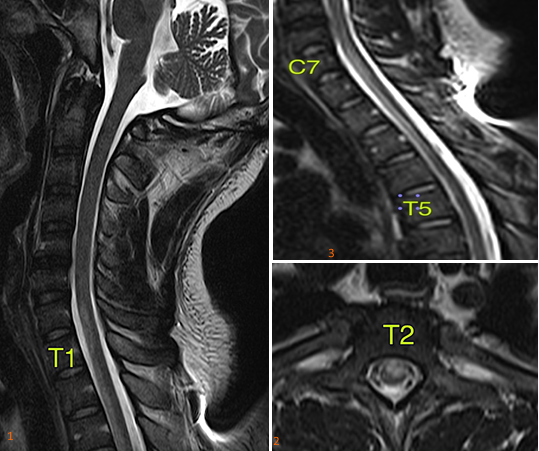

Spontaneous anterior spinal cord syndrome is uncommon and very rare in young adults. It affects the vascularization of the anterior 2/3 of the spinal cord, causing acute motor paralysis and sensory loss (pain and temperature) below the level of injury. Any vascular process that limits and interferes with the blood flow in the spinal cord region may be the etiologic cause. However, spontaneous,  thrombophilia causes in young adults have rarely been reported in the world literature. Antithrombin III (ATIII) is a blood protein that blocks the formation of abnormal blood clots and, at low levels predisposes to thrombus formation, favoring the occurrence of thromboembolic events in various organs. ATIII deficiency has remarkably higher risk rates for thromboembolic events, than those reported for other thrombophilia. In addition, thrombosis can occur early and recurrently. Thrombosis is a complex disease, and ATIII deficiency shows remarkably heterogeneous clinical range with vascular events from a young age and recurrently. The onset of the hematologic picture can vary greatly, as environmental as well as genetic factors interfere in the modulation of the biological and clinical phenotypes of thrombosis related to antithrombin deficiency (Figure 1).

Figure 1 Sagittal T2-weighted sequence of the spine with signal alteration in the anterior third of the spinal cord. 2. axial T2-weighted sequence observes signal alteration in the anterior third of the spinal cord with predominance of grey matter involvement. With predominance of involvement in the gray matter. 3. extension of the alteration in the anterior third of the spinal cord (C7-T5).